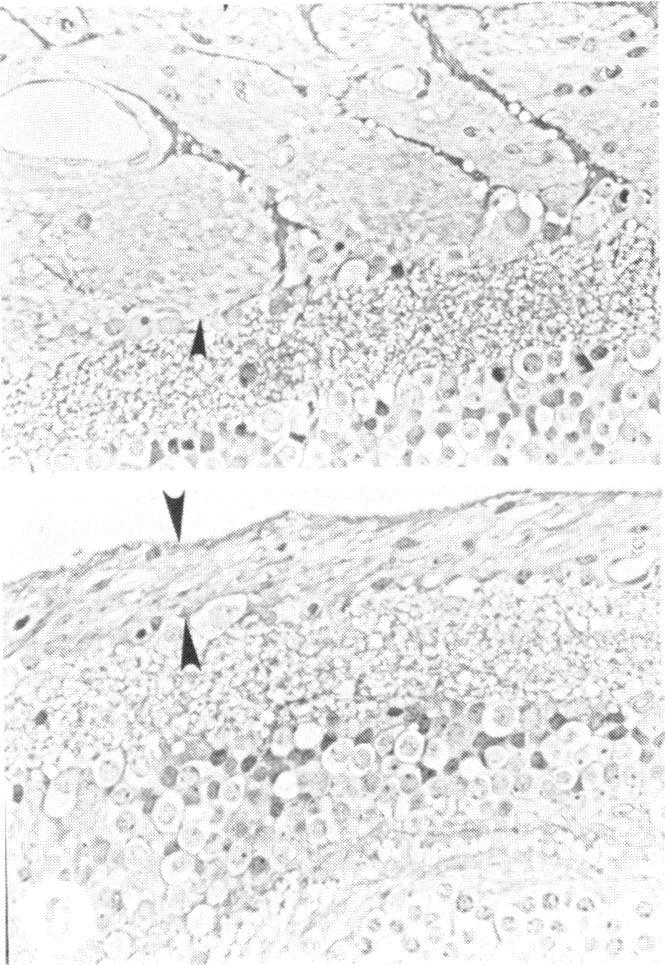

Examination of the retinal nerve fiber layer in the recognition of early glaucoma damage.

Trans Am Ophthalmol Soc. 1986;84:920-66.

Examination of the retinal nerve fiber layer in the recognition of early glaucoma damage.视网膜神经纤维层检查在早期青光眼损害识别中的应用